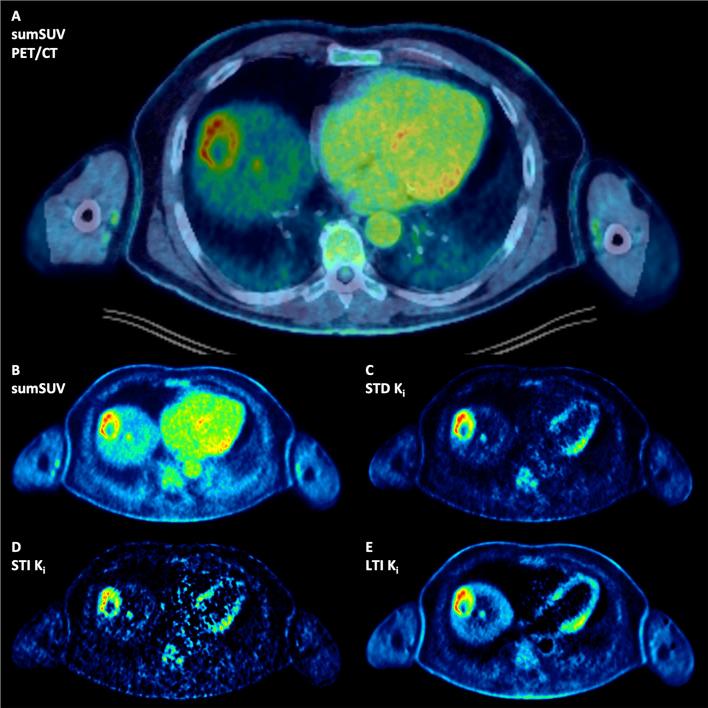

50 oncological patients with 346 tumor lesions were enrolled in the study. All patients underwent [F]FDG PET/CT (skull to upper thigh). Here, the Image-Derived-Input-Function) (IDIF) from the descending aorta was used as the exclusive input function. Four sets of images have been reviewed visually and evaluated quantitatively using the target-to-background (TBR) and contrast-to-noise ratio (CNR): short-time (30 min)-direct (STD) Patlak K, short-time (30 min)-indirect (STI) Patlak K, long-time (59.25 min)-indirect (LTI) Patlak K, and 50-60 min SUV (sumSUV). VOI-based 2TCM was used for the evaluation of tumor lesions and normal tissues and compared with the results of Patlak model.

No significant differences were observed between the four approaches regarding the number of tumor lesions. However, we found three discordant results: a true positive liver lesion in all Patlak K images, a false positive liver lesion delineated only in LTI K which was a hemangioma according to MRI and a true negative example in a patient with an atelectasis next to a lung tumor. STD, STI and LTI K images had superior TBR in comparison with sumSUV images (2.9-, 3.3- and 4.3-fold higher respectively). TBR of LTI K were significantly higher than STD K. VOI-based k showed a 21-fold higher TBR than sumSUV. Parameters of different models vary in their differential capability between tumor lesions and normal tissue like Patlak K which was better in normal lung and 2TCM k which was better in normal liver. 2TCM K revealed the highest correlation (r = 0.95) with the LTI Patlak K in tumor lesions group and demonstrated the highest correlation with the STD Patlak K in all tissues group and normal tissues group (r = 0.93 and r = 0.74 respectively).

50例患有346个肿瘤病变的肿瘤患者纳入本研究。所有患者均接受了[F]FDG PET/CT(从头颅到大腿上部)检查。在此,将降主动脉的图像衍生输入函数(IDIF)用作唯一的输入函数。四组图像已进行视觉检查,并使用靶本比(TBR)和对比噪声比(CNR)进行定量评估:短时间(30分钟)直接(STD)Patlak K、短时间(30分钟)间接(STI)Patlak K、长时间(59.25分钟)间接(LTI)Patlak K以及50-60分钟SUV(总SUV)。基于感兴趣区(VOI)的2TCM用于评估肿瘤病变和正常组织,并与Patlak模型的结果进行比较。

在肿瘤病变数量方面,四种方法之间未观察到显著差异。然而,我们发现了三个不一致的结果:所有Patlak K图像中一个真正的肝脏阳性病变、仅在LTI K中勾勒出的一个假阳性肝脏病变(根据MRI为血管瘤)以及一名肺肿瘤旁有肺不张患者中的一个真正阴性病例。与总SUV图像相比,STD、STI和LTI K图像具有更高的TBR(分别高出2.9倍、3.3倍和4.3倍)。LTI K的TBR显著高于STD K。基于VOI的k显示其TBR比总SUV高21倍。不同模型的参数在区分肿瘤病变和正常组织的能力方面有所不同,如Patlak K在正常肺组织中表现更好,而2TCM k在正常肝脏组织中表现更好。2TCM K在肿瘤病变组中与LTI Patlak K的相关性最高(r = 0.95),在所有组织组和正常组织组中与STD Patlak K的相关性最高(分别为r = 0.93和r = 0.74)。